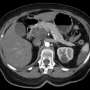

The new drug, which has shown promising results in clinical trials, targets the specific mutations found in pancreatic tumors, offering a customized approach that could potentially extend life and improve quality of care for many patients. Researchers report that the drug has significantly shrunk tumors in initial trial participants, leading to a surge of optimism among oncologists.

Authorities confirm that this innovative therapy represents a pivotal moment in cancer treatment, particularly for patients who have exhausted other options. The emotional toll on patients and families is immense, as pancreatic cancer typically presents late and is often resistant to existing treatments.